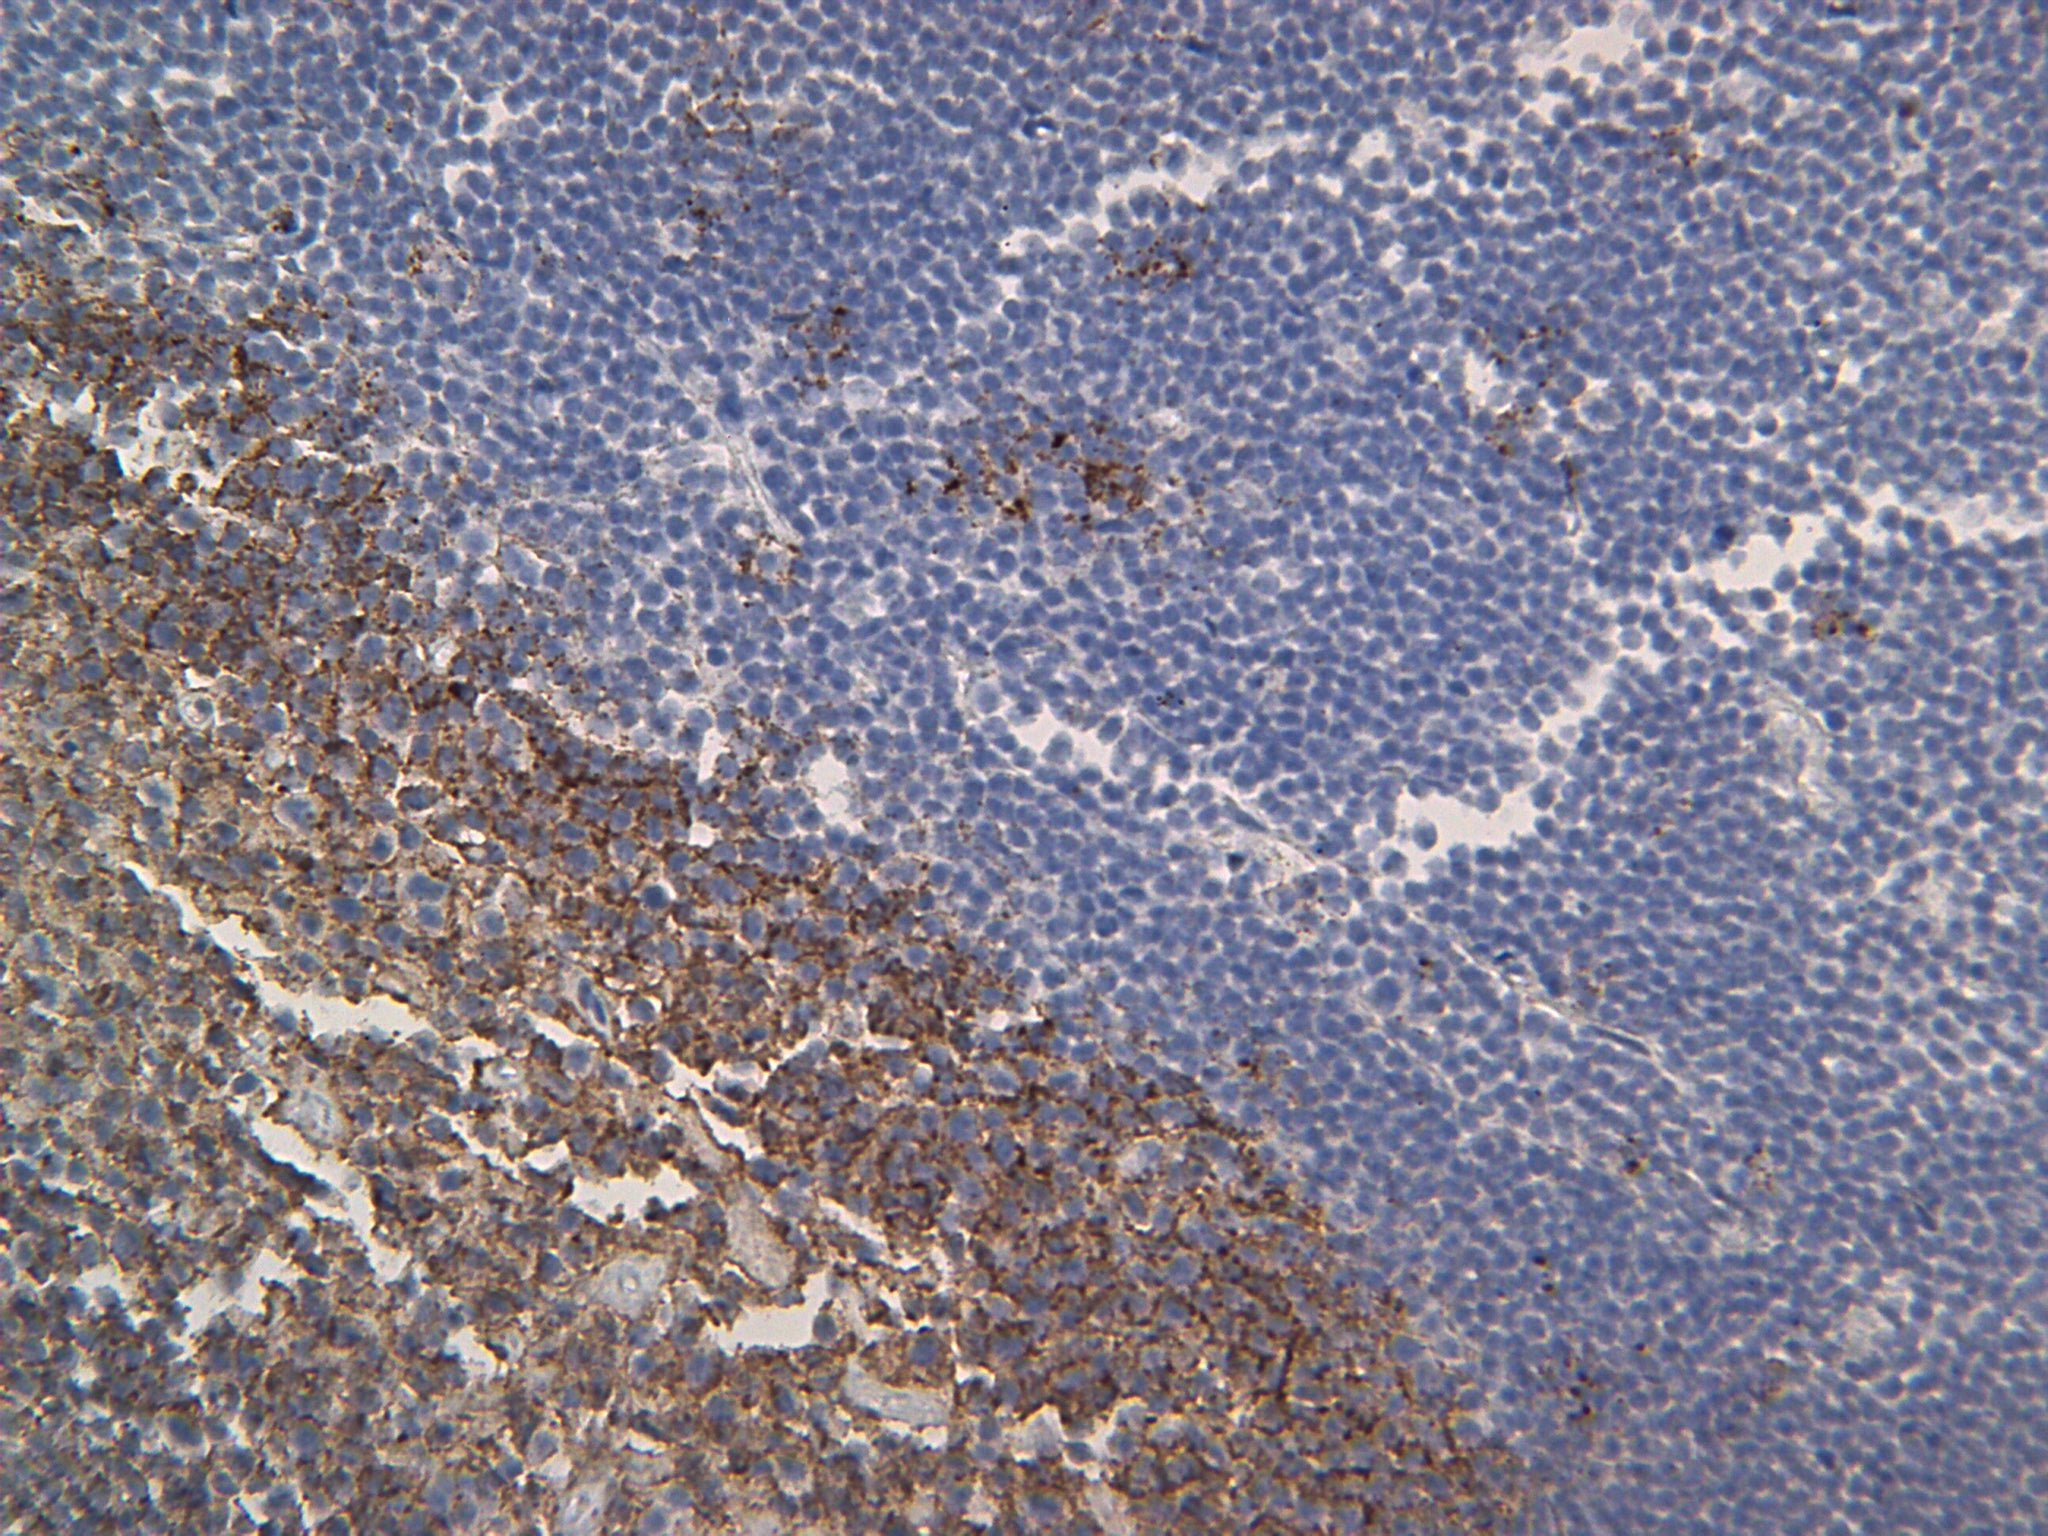

Description: This monoclonal antibody targets the C-terminal (intracytoplasmic) epitope of CD20, which is a 33 kDa leukocyte surface antigen that plays a role in the development and differentiation of B-cells into plasma cells. Although CD20 has been shown to be expressed from pre-B-cells and persisting through B-cell maturation until differentiation into plasma cells it has also been reported in low levels on normal and neoplastic T-cells.

Studies have shown that CD20 is a reliable pan B-cell marker and in conjunction with a T-cell marker (CD3) for immunophenotyping B-cell lymphomas from T- and null-cell lymphomas.

Positive Control: Lymph node, tonsil, or B-cell lymphoma